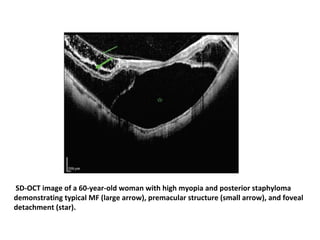

• OCT AND MF

• The standard test to detect MF remains OCT

On OCT scans

• eyes with MF exhibit a thickened retina in the posterior pole

and hyporeflective splitting between the less reflective outer

retina and the more reflective inner retina.

There is splitting of the retinal layers of the macula in the presence of myopic

foveoschisis as seen on this OCT scan.

SD-OCT image of a 60-year-old woman with high myopia and posterior staphyloma

demonstrating typical MF (large arrow), premacular structure (small arrow), and foveal

detachment (star).

On OCT scans •eyes with MF exhibit a thickened retina in the posterior pole and hyporeflective splitting between the less reflective outer retina and the more reflective inner retina. • There is splitting of the retinal layers of the macula in the presence of myopic foveoschisis as seen on this OCT scan.

• 73.

SD-OCT image ofa 60-year-old woman with high myopia and posterior staphyloma demonstrating typical MF (large arrow), premacular structure (small arrow), and foveal detachment (star).